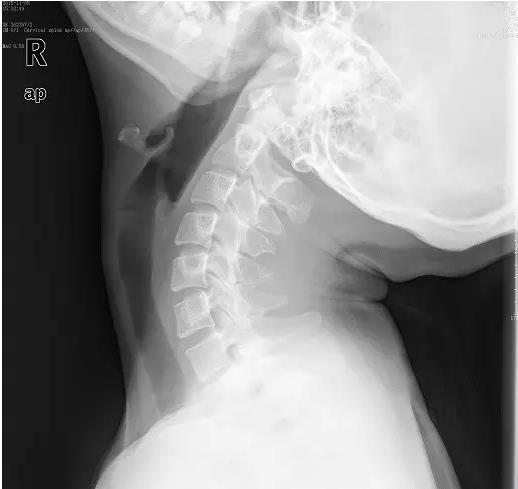

近日门诊接诊了一位18岁的花季少女小美,说是颈部疼痛难忍,已经半个月了,实在疼的不行了才来医院看看。拍片后显示:颈椎退变,生理弧度消失、变直。下面这张就是小张的颈椎侧位片。片子上,颈椎排列略呈“S”形。而不象是正常的“C”形。